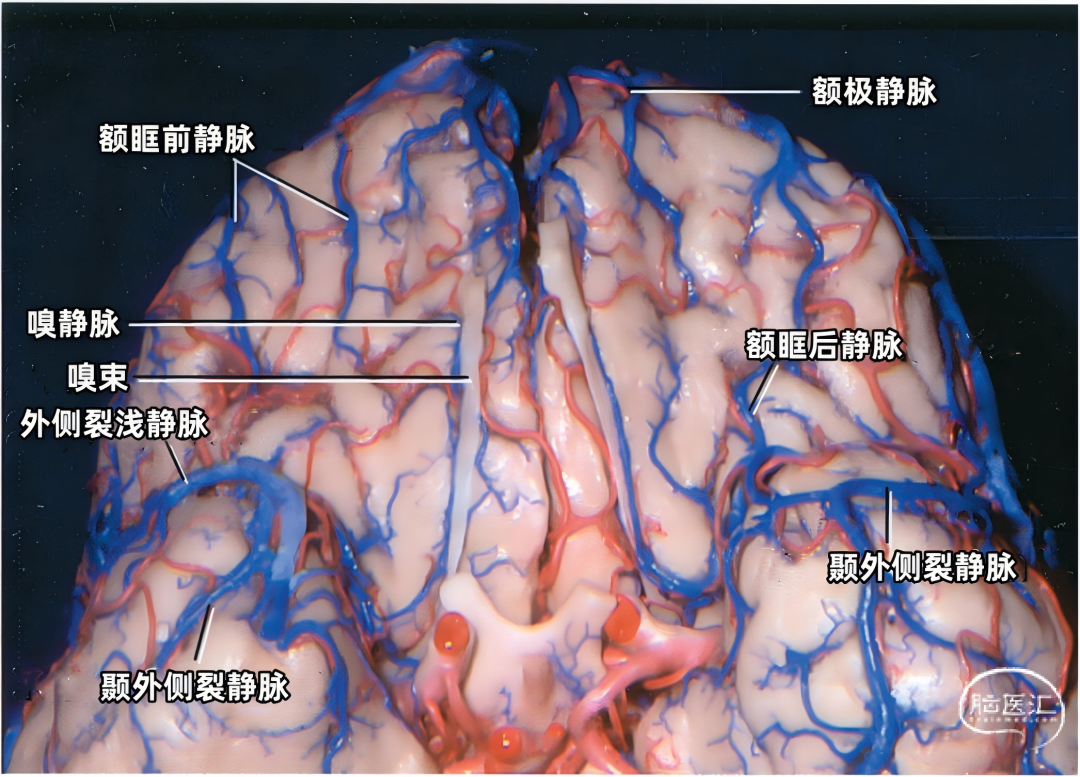

额叶底面(蓝色)由额极静脉、眶额前静脉、眶额后静脉,嗅静脉和终板旁静脉引流。 颞叶底面(绿色)由颞底前静脉、颞底中静脉、颞底后静脉、海马前静脉、钩回静脉、颞内侧静脉、颞外侧裂静脉。

额叶底面的静脉按引流方向由两种蓝色标出:浅蓝色为前组静脉,进入上矢状窦。深蓝色为后组静脉,进入基底静脉前端。额底静脉的前组是眶额前静脉;后组包括眶额后静脉和嗅静脉。 颞叶底面的静脉按引流方向由两种绿色标出:深绿色标注的静脉向外侧走行汇入小脑幕窦。浅绿色标注的静脉向内侧走行汇入基底静脉。向外侧走行的颞底静脉包括颞底前静脉、颞底中静脉、颞底后静脉;向内侧走行的颞底静脉包括海马前静脉、钩回静脉、颞内侧静脉。 枕叶底面只有一支即枕下静脉,由紫色标出,汇入小脑幕窦。大脑内静脉汇入Galen静脉。

额叶的引流静脉分为外侧面组、内侧面组、底面组。外侧面组分为上升组,汇入上矢状窦;下降组,引流向外侧裂,进入外侧裂浅静脉。 上升组静脉包括额极、额前、额中、额后静脉,中央前静脉和中央沟静脉。这些静脉可能在回流至上矢状窦前与相邻的底面组、内侧面组的静脉汇合; 下降组由额外侧裂静脉组成。上升组引流的区域大于下降组。 额叶外侧面静脉及其引流区域如下:额极静脉引流额下回、额中回和额上回前部;额前、额中、额后静脉引流额极和中央前回之间的额叶前、中、后部凸面;中央前静脉引流中央前回下部、额下回盖部和邻近的额下、额中和额上回;中央Rolandic静脉引流中央沟附近的中央前回和中央后回;额外侧裂静脉引流额下回和邻近的额中回下部及中央前回下部。 额叶内侧面由弯曲的扣带沟分为内侧区和外侧区。额内侧静脉分为上升组进入上矢状窦;下降组进入下矢状窦或汇入行经胼胝体的静脉,最后进入基底静脉前端。上升组静脉由前内侧额静脉、中内侧额静脉、后内侧额静脉和旁中央沟静脉组成,它们是额上回内侧和邻近扣带回的主要静脉回流,一般向上弯曲走行,在半球上缘向外加入来自半球外侧组的静脉,然后注入上矢状窦。下降组静脉包括胼周前静脉、终板旁静脉和大脑前静脉。 额叶内侧面静脉及其引流区域如下:额前内侧静脉引流额极后方的扣带回和额上回;额中间内侧静脉引流胼胝体膝部前方的额上回和邻近扣带回的内侧面;额后内侧静脉引流胼胝体膝部上方的额上回和扣带回;旁中央静脉引流胼胝体体部上方的扣带回和邻近的旁中央小叶;胼周前静脉为成对的静脉,引流胼胝体膝部和嘴部,以及邻近的扣带回;大脑前静脉引流胼胝体嘴部以下至视交叉上缘之间的区域;终板旁静脉引流胼胝体嘴部下方的终板旁回和嗅旁回区域。 额下静脉组,引流额叶眶面区域,可分为前组和后组:前组流向额极注入上矢状窦;后组引流向后,在外侧裂内侧集中于前穿质表面,形成基底静脉。前组由额眶前静脉和额极静脉组成;后组由嗅静脉和额眶后静脉组成。 额下静脉及其引流区域如下:额眶前静脉引流直回前部和眶回前内侧部;额眶后静脉引流额叶眶面后部;嗅静脉引流嗅沟及其邻近的直回和内侧眶回。

下图示额叶眶面,由额极静脉、额眶前静脉、额眶后静脉、嗅静脉引流。额眶前静脉汇入上矢状窦前部或其分支。额眶后静脉注入前穿质下方的静脉,形成基底静脉的前端。

嗅静脉、终板旁静脉、大脑前静脉和额眶后静脉汇合于基底静脉前端。

下图示左侧前穿质下方区域的放大观。嗅静脉、大脑前静脉、额眶后静脉、外侧裂深静脉汇集形成基底静脉。脑室下静脉在大脑脚后缘汇入基底静脉。